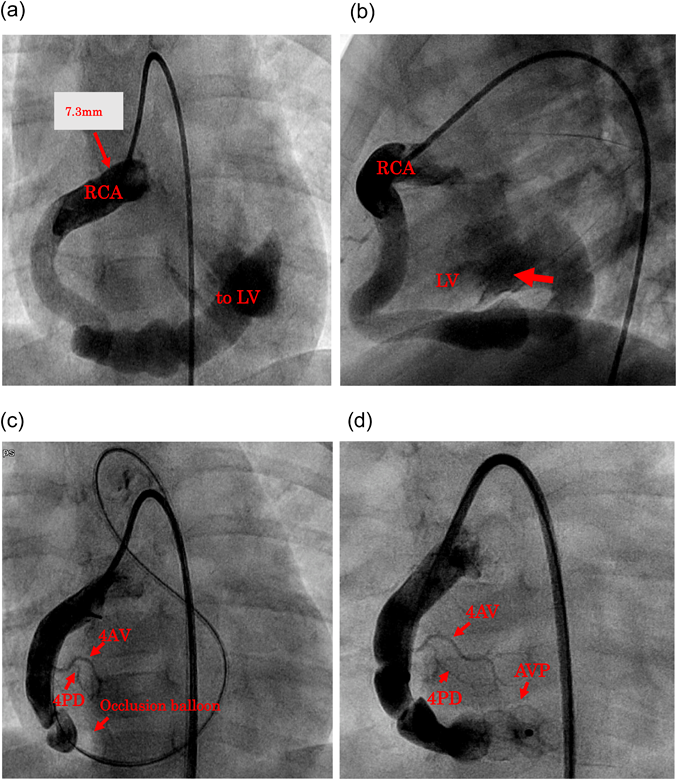

One year and 5 months after the intervention, the patient underwent RCA angiography to evaluate changes in the RCA following CAF closure. The proximal portion of the RCA was patent. There had been a caliber change there, with a vessel diameter of approximately 1.6 mm (Fig. 2). Therefore, antiplatelet agents and anticoagulants were continued.

Fig. 2 RCA angiography 1 year and 5 months after implantation of the occluder. The caliber of the RCA near its origin had changed remarkably

4AV, #4 atrioventricular branch; 4PD, #4 posterior descending branch; RCA, right coronary artery.

Additionally, the affected coronary artery could become slender, stenotic or even occluded over time after CAF closure. Such obstruction, although complete occlusion is rare, may not present obvious ischemic symptoms, because the contralateral coronary arterial system could supply blood flow to the myocardium of the affected area.19) Even if a patient is asymptomatic, periodic coronary angiography and myocardial scintigraphy are considered essential to clarify whether any clinically significant stenosis is present across the affected coronary arterial pathway. In our patient, it was found obvious that the caliber at the RCA origin had changed on coronary angiography within one year after CAF closure. We decided to continue antiplatelet and anticoagulant therapy, since narrowing might develop still further eventually. As for pericardial effusion and a mild decrease in LV contraction seen after the procedure, we considered that inflammatory response to the device placed was the pathophysiological cause. Aspirin, a diuretic, and a vasodilator orally administered were effective, providing rapid improvement in these phenomena.